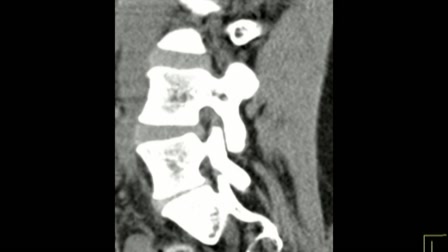

Szenzomotoros amnézia és a gerincsérv kapcsolata! www.gerincem.hu